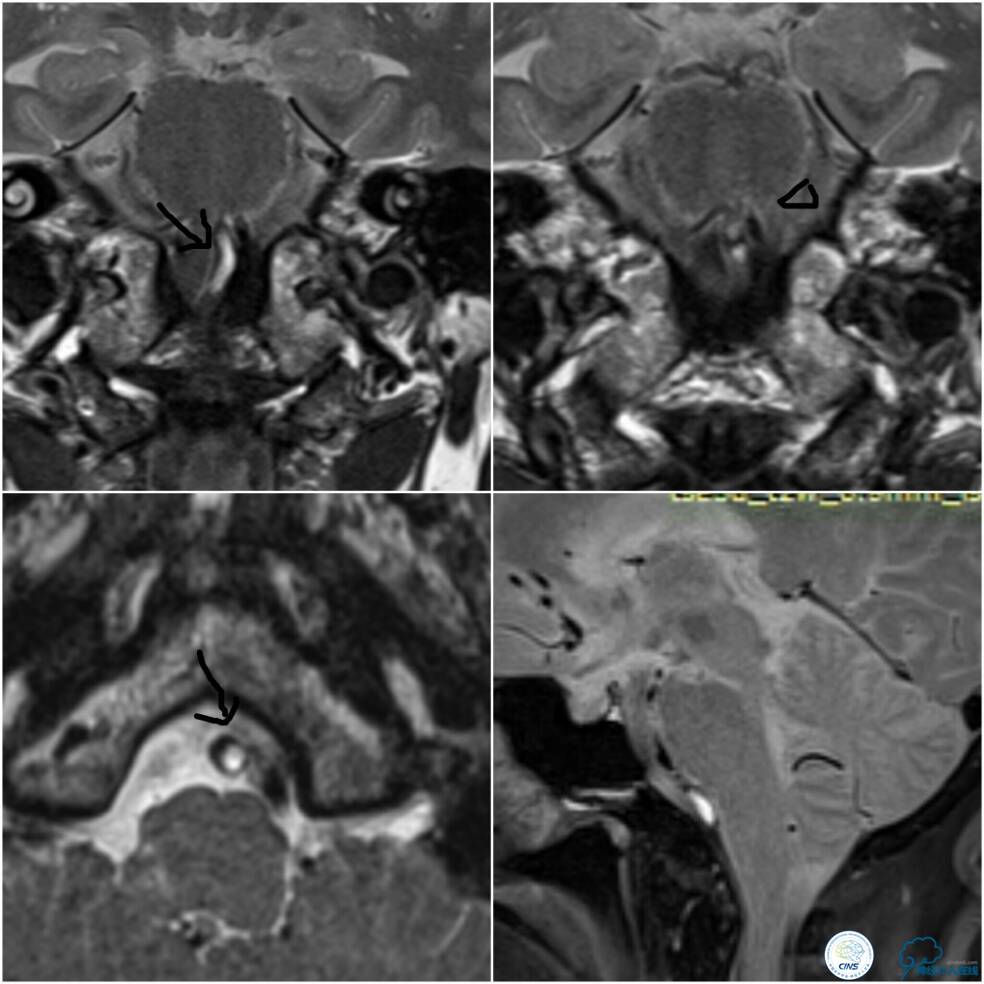

病后就诊当地医院,予以双抗+积极控制危险因素治疗,但症状持续无缓解,就诊期间核磁检查提示右延髓新近脑梗死,MRA示双椎及基底动脉显示欠佳(图1)。

图1